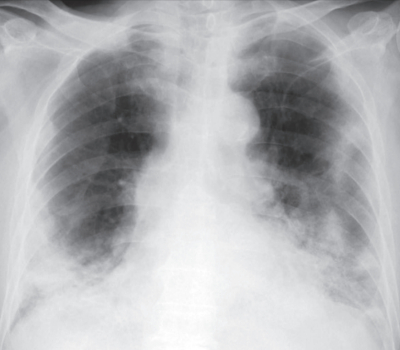

血液所見:赤血球 470万、Hb 14.2 g/dL、白血球 4,800、血小板 1.0万、PT-INR 2.4(基準 0.9~1.1)。血液生化学所見:LD 629 U/L(基準 120~245)、尿素窒素 23 mg/dL、クレアチニン 0.9 mg/dL、血糖 128 mg/dL。CRP 10 mg/dL。動脈血ガス分析(リザーバー付マスク 10L/分 酸素投与下):pH 7.40、PaCO2 42Torr、PaO2 64Torr、HCO3- 24mEq/dL。心電図:正常洞調律。胸部エックス線写真と胸部CTを別に示す。唾液を用いたSARS-CoV-2のPCR検査は陽性であった。